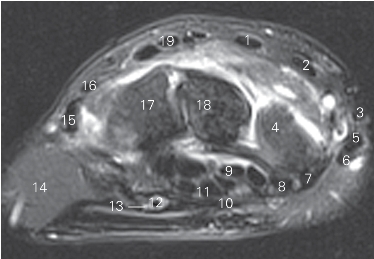

图4-44 经腕掌关节的横断层MR T2WI FS

1 头状骨 capitate bone 2 桡侧腕短伸肌 extensor carpi radialis brevis

3 拇长屈肌 flexor pouicis longus

4 桡侧腕长伸肌腱 tendon of extensor carpi radialis longus

5 小多角骨trapezoid bone 6 大多角骨trapezium bone

7 桡侧腕屈肌腱 tendon of flexor carpi radialis

8 大鱼际thenar

9 指浅屈肌腱 tendon of flexor digitorum superficialis

10 指深屈肌腱 tendon of flexor digitorum profundus

11 掌腱膜palmar aponeurosis 12 尺神经ulnar nerve

13 小鱼际hypothenar 14 第五掌骨5th metacarpal bone

15 小指伸肌腱 tendon of extensor digiti minimi

16 第四掌骨4th metacarpal bone

17 指伸肌腱 tendon of extensor digitorum

图4-45 经远侧列腕骨间的横断层MR T2WI FS

1 桡侧腕短伸肌 extensor carpi radialis brevis

2 桡侧腕长伸肌 extensor carpi radialis longus

3 拇长伸肌 extensor pollicis longus 4 舟骨 scaphoid bone

5 拇短伸肌 extensor pollicis brevis 6 拇长展肌 abductor pollicis longus

7 桡侧腕屈肌 flexor carpi radialis

8 拇长屈肌 flexor pouicis longus

9 指深屈肌 flexor digitorum profundus

10 腕管支持带 tenaculum of carpal canal

11 指浅屈肌 flexor digitorum superficialis

12 尺管 ulnar canal 13 尺神经 ulnar nerve

14 小鱼际 hypothenar

15 尺侧腕伸肌 extensor carpi ulnaris 16 小指伸肌 extensor digiti minimi

17 钩骨 hamate bone 18 头状骨 capitate bone

19 指伸肌 extensor digitorum